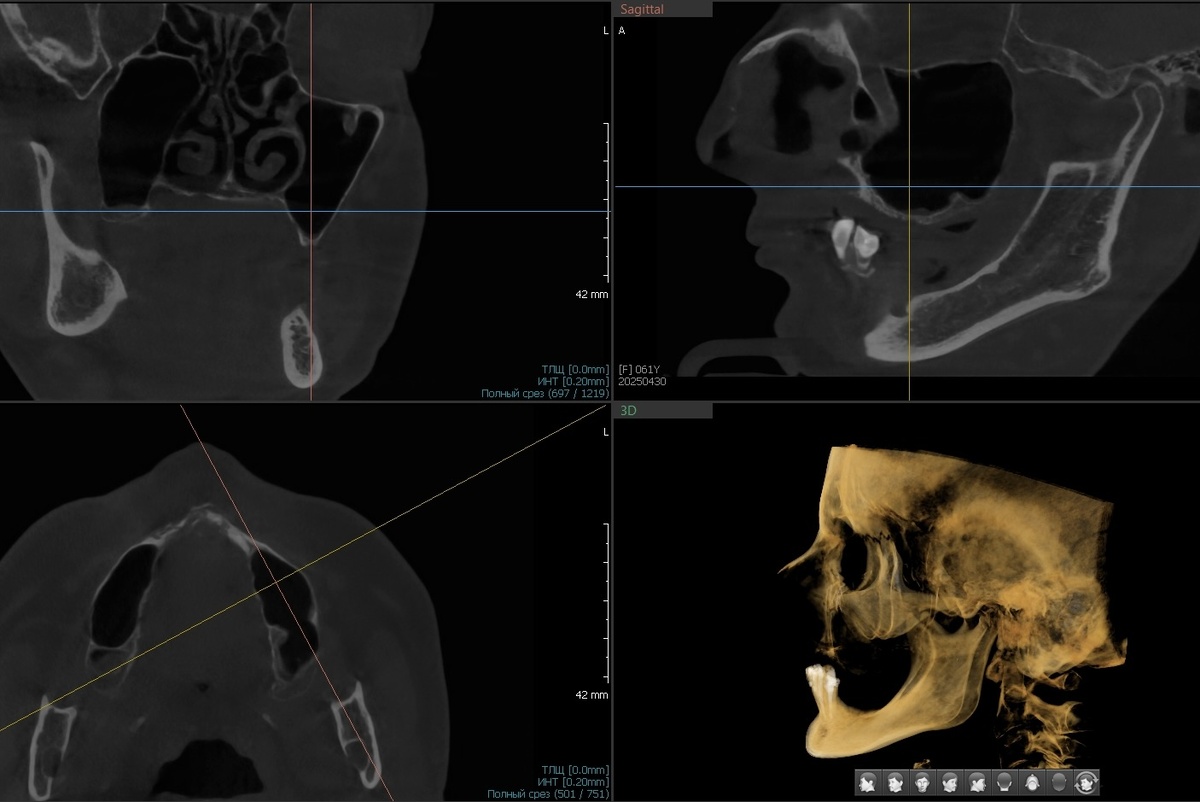

Посмотрите на скрины КТ верхней челюсти (листайте):

Кости нет. Можно сказать прямо - альвеолярный отросток на грани исчезновения, то, что от него осталось, костью полноценной не назовёшь.

Пациентка длительное время пользовалась съёмными протезами - полный съёмный на верхней челюсти, частичный - на нижней. Под давлением протезов кость атрофировалась. Не фигурально - объективно. Даже самые маленькие имплантаты некуда устанавливать.

• Синус-лифтинг? Бесполезно. Объём материала, который нужно заложить под мембрану - огромный. А кости нет. Значит, нет питания для того, чтобы подсаженный материал преобразовался в собственную кость. Не вывезет организм этого в данном случае.

• Подсаживать костные блоки, ставить титановые сетки - нежизнеспособно по той же причине. Не прорастёт, не приживётся. Нет питания - нет шансов на адекватную реабилитацию.